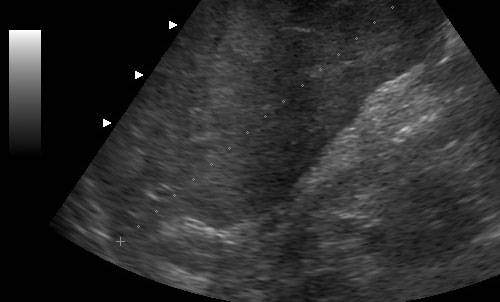

Ультразвуковая диагностика

Ультразвуковое исследование является наиболее доступным и дешевым методом обследования. Оно позволяет точно определять размеры печени, а также выявлять аномалии развития и такие заболевания, как цирроз, онкология и метастазы, гепатит.

Определить наличие проблем с печенью можно при обычной ультразвуковой диагностике. Это исследование позволяет оценить характер заболевания, получить сведения о его протекании, а также назначать и корректировать лечение.

Каждый врач, специализирующийся на проведении УЗИ, знает, на что необходимо обратить внимание в первую очередь. Так, диагност оценивает плотность, структуру органа, проверяет, нет ли патологических включений. Помимо этого, обязательно смотрят размеры печени на УЗИ. Норма у взрослых установлена для каждой ее доли. Также оценивается ее косой поперечный размер. При проведении исследования врач смотрит состояние желчевыводящих путей и крупных сосудов, проходящих внутри печени.

Для того чтобы оценить, все ли в порядке с этим органом, необходимо знать, какая норма УЗИ печени, каковы нормальные показатели печени. Она должна быть однородной структуры, без уплотнений, крупные вены должны легко визуализироваться. Контуры ее должны быть четкими и ровными. Также должен быть виден желчный пузырь и протоки. На всем протяжении должна визуализироваться нижняя полая вена, диаметр ее может быть от 9 до 15 мм. А вот внутрипеченочные протоки в норме должны прослеживаться с трудом.

Структура печени обладает умеренной эхогенностью, которая выше, чем показатели почек, однако же, меньше, чем аналогичный параметр у поджелудочной железы. При осмотре органа отсутствует гомогенность, т.к. она снабжена кровеносными сосудами.

В первую очередь, при обследовании органа врач-узист определяет «хвостатую» долю печени, чтобы ошибочно не выдать ее за новообразование. Связано это с тем, что плотная структура круглой связки чрезмерно отражает ультразвук и в итоге хвост становится менее эхогенным. Но, в общем, паренхима в норме хорошо пропускает ультразвук и дает возможность осмотреть даже самые глубокие ткани, как правой доли, так и левой. Вены в норме также хорошо и беспрепятственно просматриваются по всей длине. Не видны только мелкие желчевыводящие протоки, толщина которых имеет менее 1 мм в диаметре, не только из-за малого размера, но и из-за крайне высокой их эхогенности.